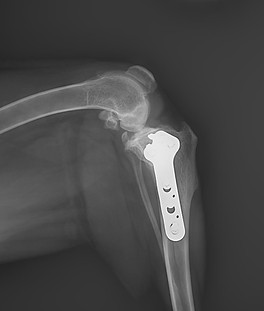

TPLO Surgery

Our clinic offers Tibial Plateau Levelling Osteotomy (TPLO) surgery, a highly effective procedure for treating cruciate ligament injuries in dogs. This advanced orthopaedic surgery involves altering the angle of the tibial plateau to stabilise the knee joint, reducing pain and restoring mobility. Our skilled veterinary team uses state-of-the-art techniques and provides compassionate post-operative care to ensure your pet’s swift and comfortable recovery.